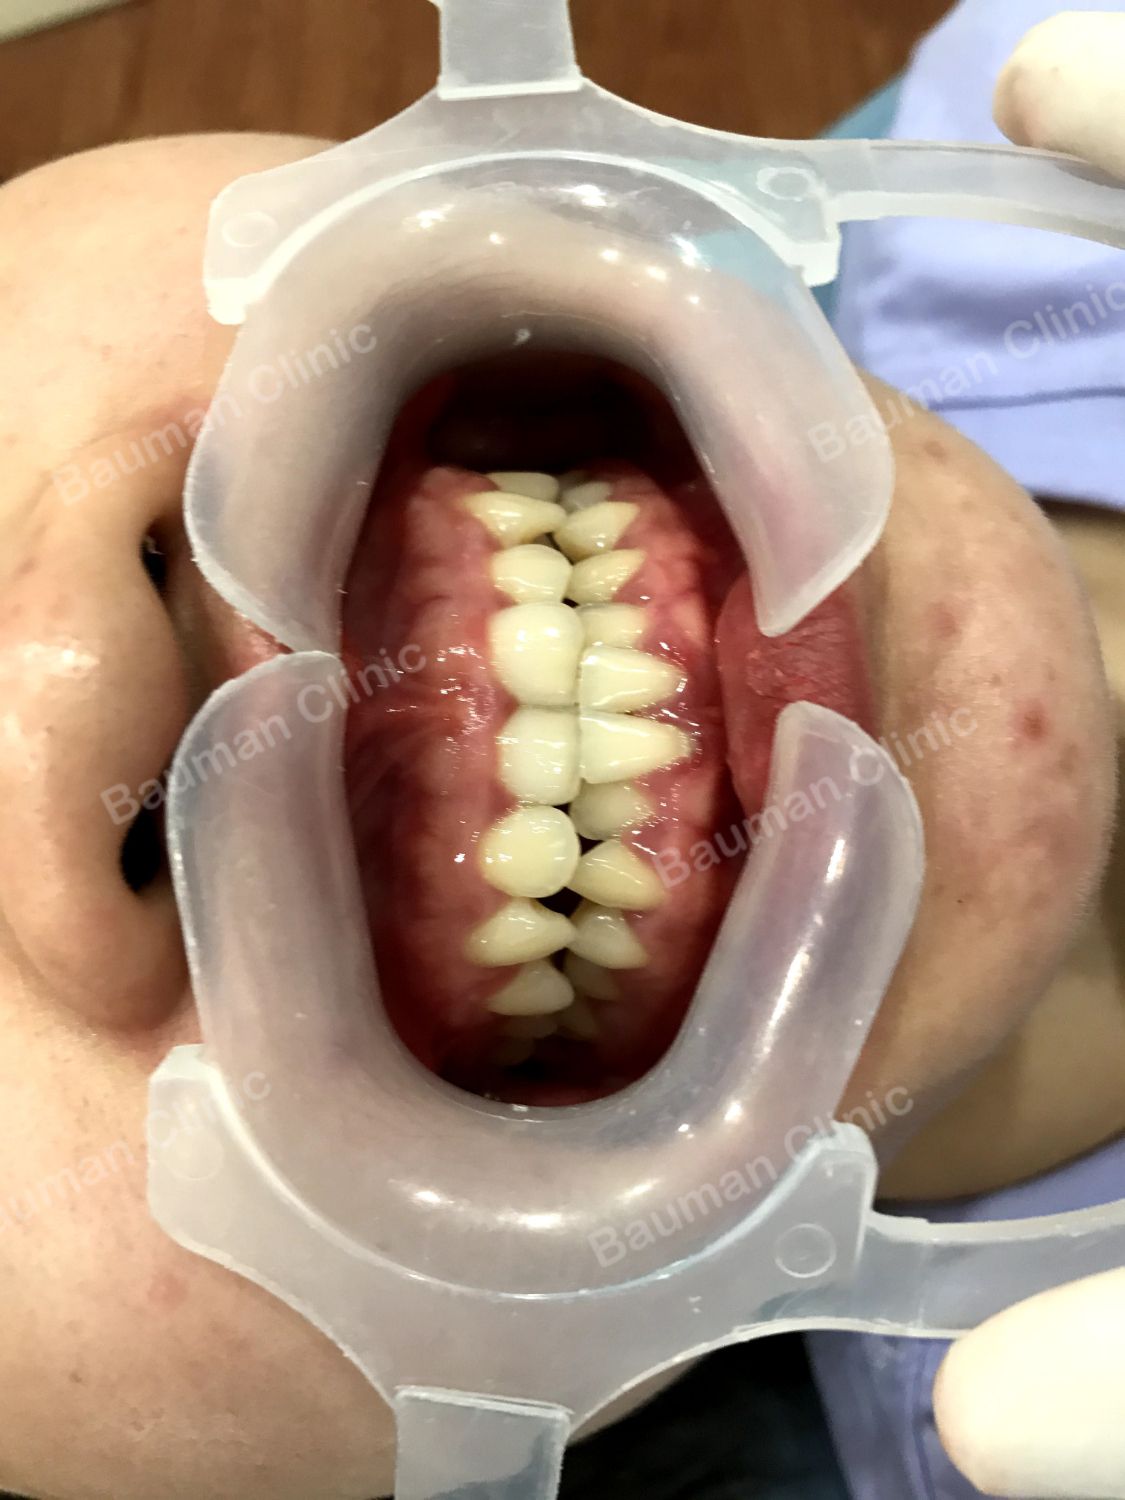

Ca niềng răng số 5015: Bạn gái xinh đẹp gặp tình trạng khớp cắn ngược khiến góc nghiêng thiếu hoàn hảo. Môi trên của bạn ấy bị lùi vào trong so với môi dưới (nhìn ở góc nghiêng bị lộ rõ). Răng chen chúc khấp khểnh nặng, lệch đường giữa.

Tuy răng chen chúc nặng nhưng trường hợp của bạn không cần nhổ răng mà vẫn có thể đạt được kết quả hoàn hảo. Hãy đến gặp bác sĩ chỉnh nha tại Nha khoa Bauman ngay nhé!